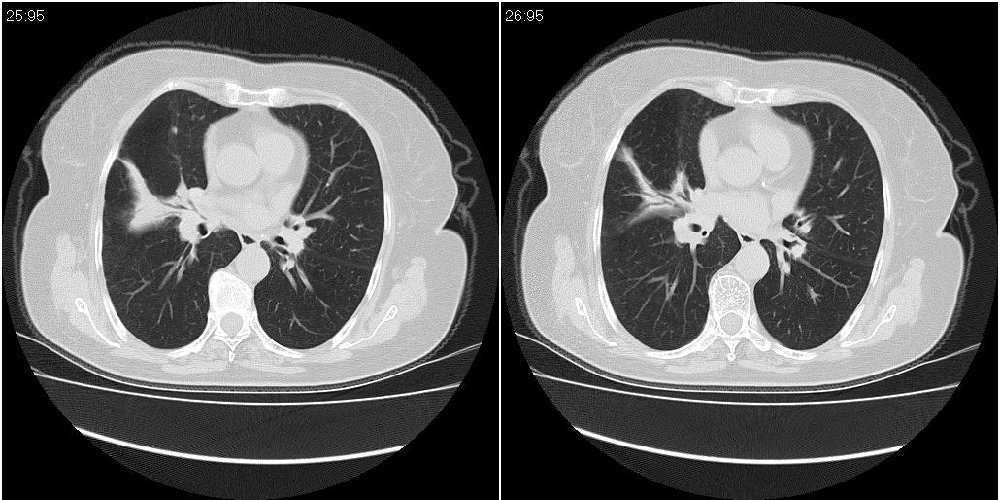

女性,72岁。去年9月份发现肺部病变,诊为肺结核并进行正规治疗至今,但复查后发现ct表现几乎没有变化。

右中间段支气管局限性狭窄,右中叶支气管亦稍显狭窄,但并未见明显占位表现,半年多了,无变化也许是好事,可能为炎性狭窄,建议继续随访。

右中间段支气管局限性狭窄,右中叶支气管亦稍显狭窄.

双肺继发性肺结核并右肺中叶节段性肺不张,左下胸膜肥厚粘连。